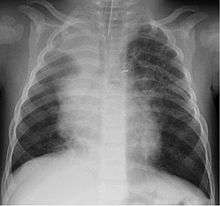

A study in Jordan found that 9% of 220 children hospitalised with lower respiratory tract infection were infected with bocavirus.[26] Of those infected the median age was 4 months. Coughing (100%), wheezing (82.7%) and fever (68.2%) were the most common clinical findings with bronchopneumonia (35%) and bronchiolitis (30%) being the most common ultimate diagnoses.

Although most cases are mild, severe respiratory disease has also been reported.[27]